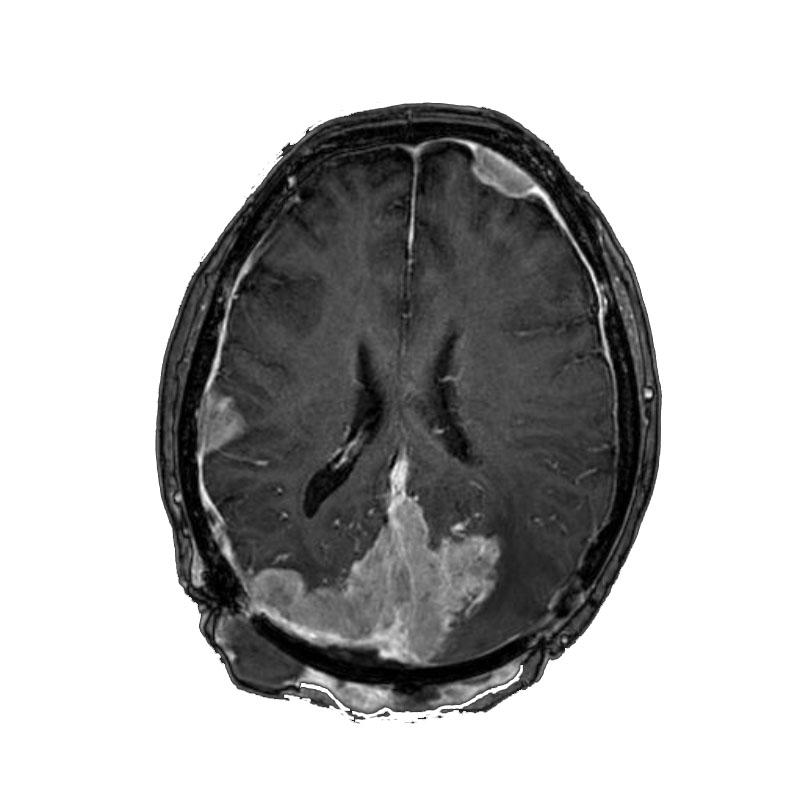

右側頭葉脳腫瘍

摘出術

南田/野本/佐伯